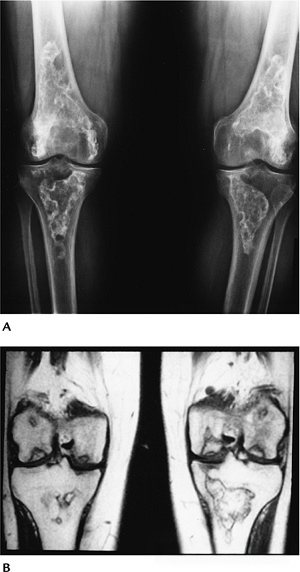

816fffc5d8097e533c37f9acac40b5e5.png

图-6骨梗死。双膝站立位X光片显示双膝典型骨梗死的蛇行状边缘钙化。T1WI显示了梗死区和软骨下缺血性坏死。